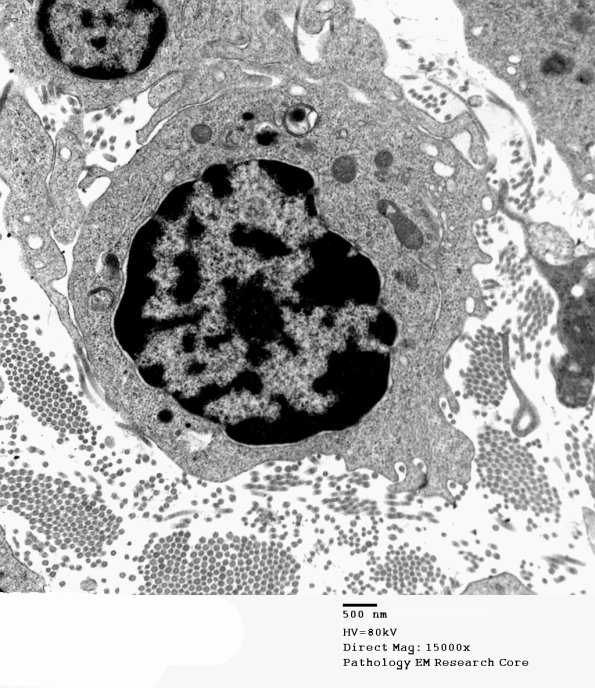

This case exhibits numerous lymphocytes within the endoneurium. (electron micrographs)